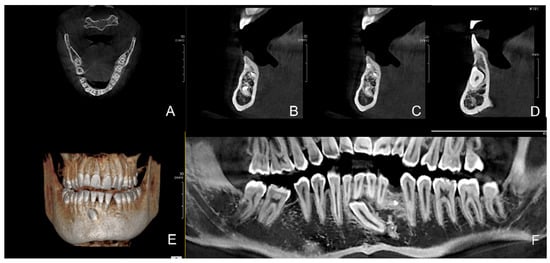

1.2. Case Number 2